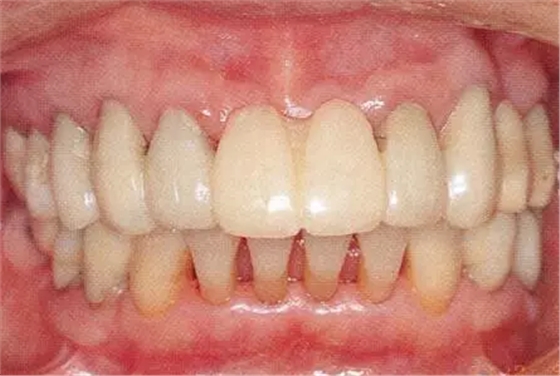

▲圖15-1,2

在正畸??漆t(yī)生處接受了正畸治療,雖然上頜正畸治療已經(jīng)完成,但由于磨牙區(qū)的邊緣嵴不整齊而導致牙體之間存在空隙。要想在這個狀態(tài)下護理牙周組織以及咬合狀況是非常困難的。由此可見,在治療時,正畸專科醫(yī)生與全科口腔醫(yī)生保持目標一致是非常重要的。